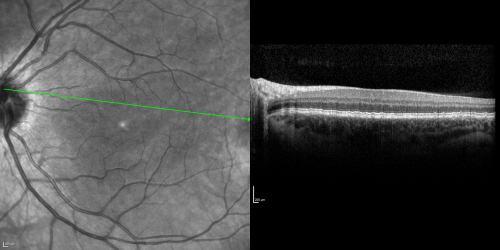

Basal Laminar Drusen - Cuticular Drusen - 19 Year Old with Lupus Nephritis

19-year-old.  She has a history of developing severe systemic lupus erythematosus in 2001.  She was in renal failure and had biopsy proven Class 2 lupus nephritis.  She is currently on Plaquenil 400 mg for six years, as well as Prednisolone orally, every other day. OD 20/20, OS 20/25.